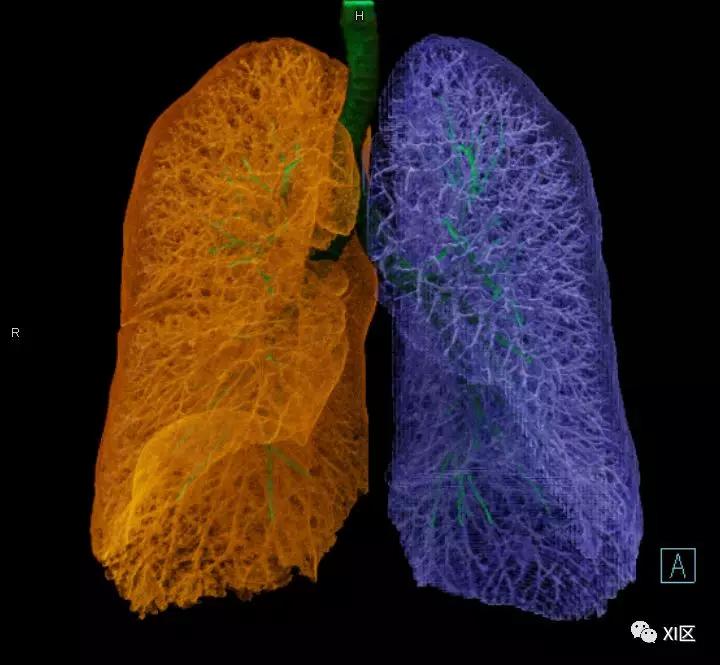

气管支气管树与两肺融合显示

肺表面重建显示叶间裂和肺的分叶

透视图显示肺的叶间裂和肺的分叶